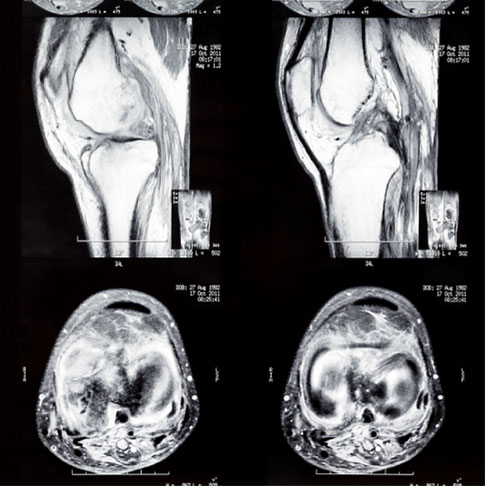

Musculoskeletal Imaging

Musculoskeletal Imaging involves viewing- interpreting medical images of bones, joints and related soft tissues and diagnosing injuries and disease.

Musculoskeletal Imaging Services

• All joints scan

• Cartilage evaluation with 3D DESS

(Dual Echo study state gradient recalled echo)